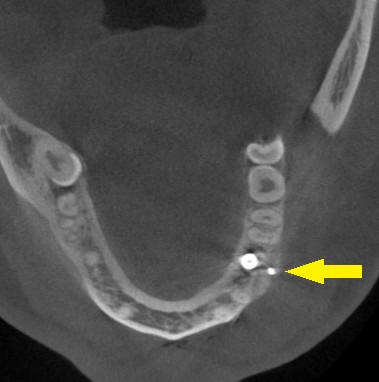

CTを撮影してみると、確かに、骨幅が狭く、十分な骨の厚みを確保してインプラントを長期に安定した状態にしたいとなると、骨を増やす手術が必要でした。

下の写真に手術前後のCTを示します。